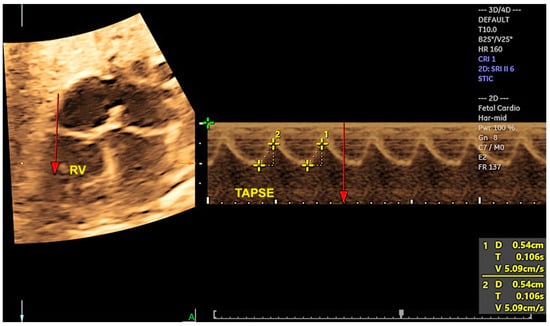

2.6. Cardiac Functional Evaluation

- Tedesco, G.D.; de Souza Bezerra, M.; Barros, F.S.; Martins, W.P.; Nardozza, L.M.; Carrilho, M.C.; Moron, A.F.; Carvalho, F.H.; Rolo, L.C.; Araujo Júnior, E. Reference Ranges of Fetal Cardiac Biometric Parameters Using Three-Dimensional Ultrasound with Spatiotemporal Image Correlation M Mode and Their Applicability in Congenital Heart Diseases. Pediatr. Cardiol. 2017, 38, 271–279. [Google Scholar] [CrossRef] [PubMed]

- Tanis, J.C.; Mohammed, N.; Bennasar, M.; Martinez, J.M.; Bijnens, B.; Crispi, F.; Gratacos, E. Online versus offline spatiotemporal image correlation (STIC) M-mode for the evaluation of cardiac longitudinal annular displacement in fetal growth restriction. J. Matern. Fetal Neonatal Med. 2018, 31, 1845–1850. [Google Scholar] [CrossRef]